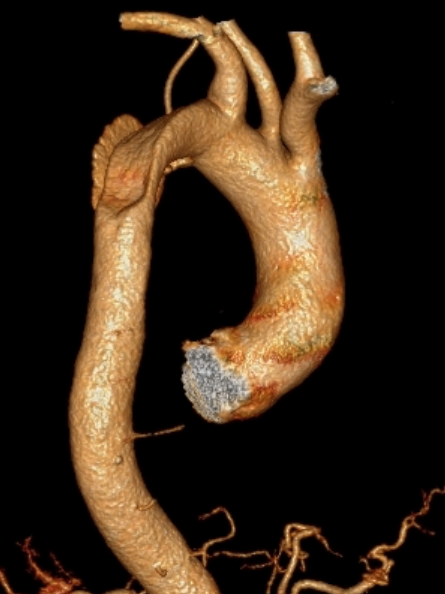

7月23日,患者黄某因突发胸背部疼痛6小时来我院急诊科就诊,来时血压高达196/126mmHg!行主动脉CTA检查,确诊为自主动脉弓至胸主动脉夹层形成(累及左锁骨下动脉),请介入血管外科、重症医学科会诊后,考虑到患者病情危重,紧急入住重症医学科进行控制血压、心率、止痛等处理。

7月30号,复查主动脉CTA,显示“主动脉夹层(Debakey III型)伴部分腔内血栓形成大致同前,不排除伴壁间血肿”。经介入血管外科组内讨论,易俊方主任考虑到患者夹层有效保守治疗后未再进展,急性期平稳渡过,决定在发病第10天为患者行“DSA下胸主动脉腔内支架隔绝术+左锁骨下动脉开窗支架植入术”。

据介入血管外科主治医师潘文疆介绍,该病例病变位置特殊,夹层已累及左锁骨下动脉,跨度大,并且发自脑部供血主要动脉之一的左椎动脉,如果单纯隔绝夹层很大可能发生内漏。既要超过又要保留左锁骨下动脉,经谨慎评估,决定采用全新支架体外开窗技术,在缩短手术时间的同时,既可以防止主动脉血管的撕脱,又能保证主要分支血管的供血。